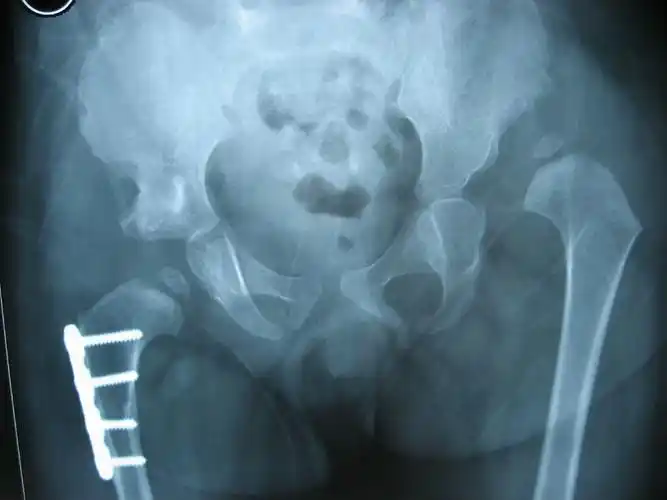

ddh包括髋关节脱位,半脱位和髋臼发